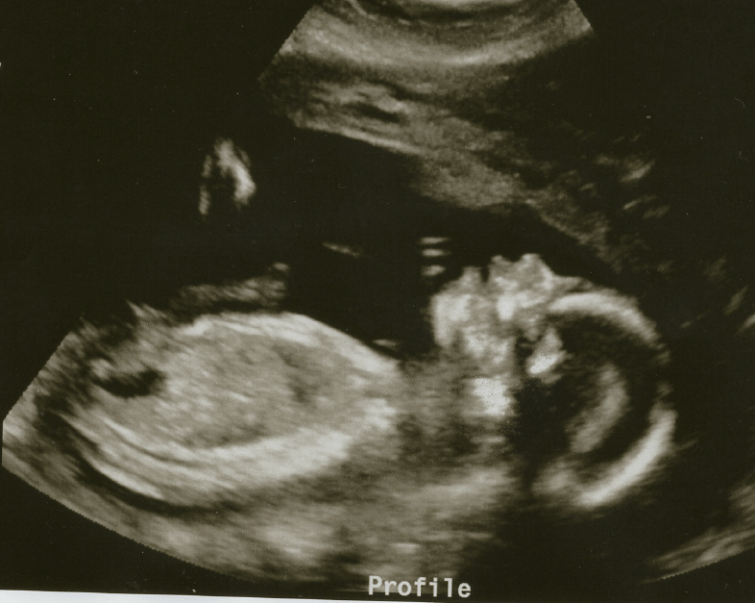

Last Friday, your Dad and I had another routine sonogram. We love going to these doctor’s appointments because we get to see you, or at the very least we get to hear your heartbeat and hiccups and tiny baby noises. This time, we got to see your little tiny features: your eyes, your mouth, your face, your feet and hands. We watched your legs kick, and your arms flail. You made a fist, and spread your fingers wide, too. At the beginning, your feet were almost above my right hip, and your head was on my left. Towards the end, you’d practiced some of your already sweet dance moves and gone almost vertical, with your feet downwards and head upwards.

We watched in awe as the technician maneuvered her apparatus to pull your organs and heart into focus to take images and measurements. She sent us home with your second set of pictures, and MY how much you’ve grown!!